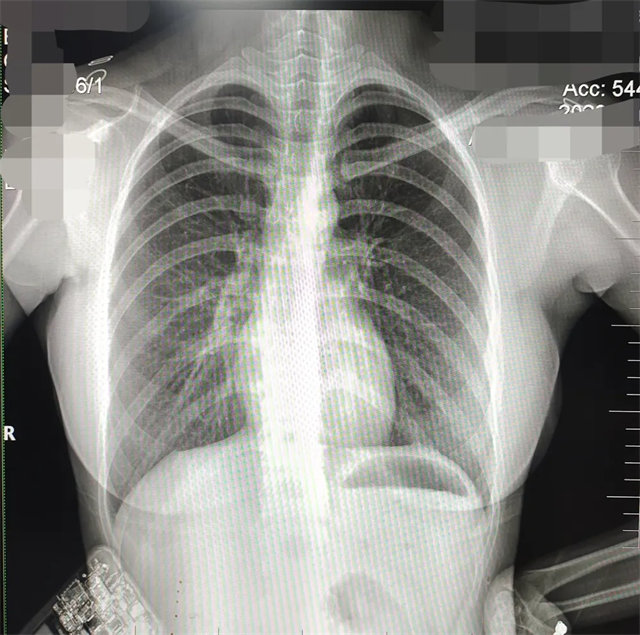

拍攝的不合格胸片的缺陷和解決方法

缺陷:兩肩胛骨未拉開肺野之外,吸氣不完全,且存在金屬飾品遮擋。

解決:去除金屬飾品及內(nèi)衣后重新按標(biāo)準(zhǔn)體位攝片即可。